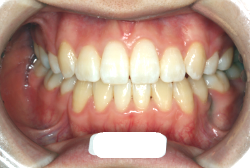

先天性欠如

「左奥歯でものが噛めない」という主訴で来院したケースです。診断の結果、基本的には「叢生」という隙間が足りないと言うことが原因の凸凹症例でしたが、左下の乳歯が高校生になってもまだ残存している状態で、そのせいで噛み合わせが極端に悪くなっていました。

検査の結果、乳歯の下には後継ぎの永久歯が先天的に欠如していました。配列の凸凹が厳しく非抜歯で矯正することは難しく、仮に無理をして非抜歯治療をしても後々「後戻り」が懸念されることから、このような症例の場合は通常、上下顎左右第一小臼歯を抜歯させていただくのですが、左下は乳歯を抜歯して、第一小臼歯は残すことにしました。これで結果として、小臼歯部を上下左右で一つずつ減らしたのと同じ状況になります。治療後は歯並びが綺麗になっただけでなく、噛み合わせ的にも正しい状態が確立しています。

このように、先天的に永久歯が足りないという症例は最近増えています。親知らずはなくても特に問題になりませんが、その他の歯が足りないと言うのは審美的にも機能的にも重大な障害となります。しかし、矯正治療を正しく行えば、結果として歯がすべてあった場合と全く同じ仕上げにすることも可能です。